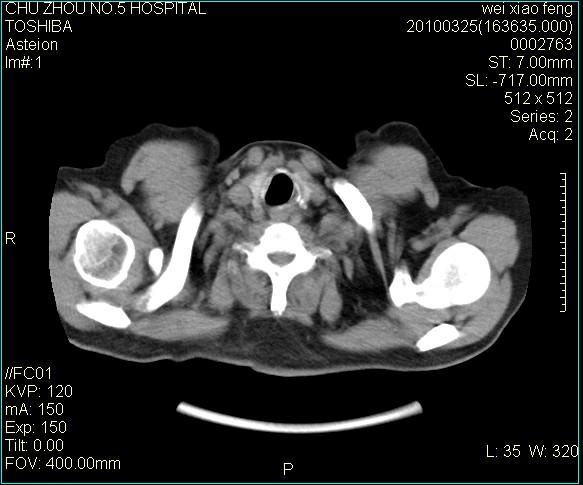

男,60岁,反复咳、痰、喘3月,加重3天。

双肺间质性改变。

间质性肺炎伴间质纤维化!不排除伴有职业病!

双肺间质纤维化,双肺血型潘散肺结核。

考虑间质性肺炎伴间质纤维化。